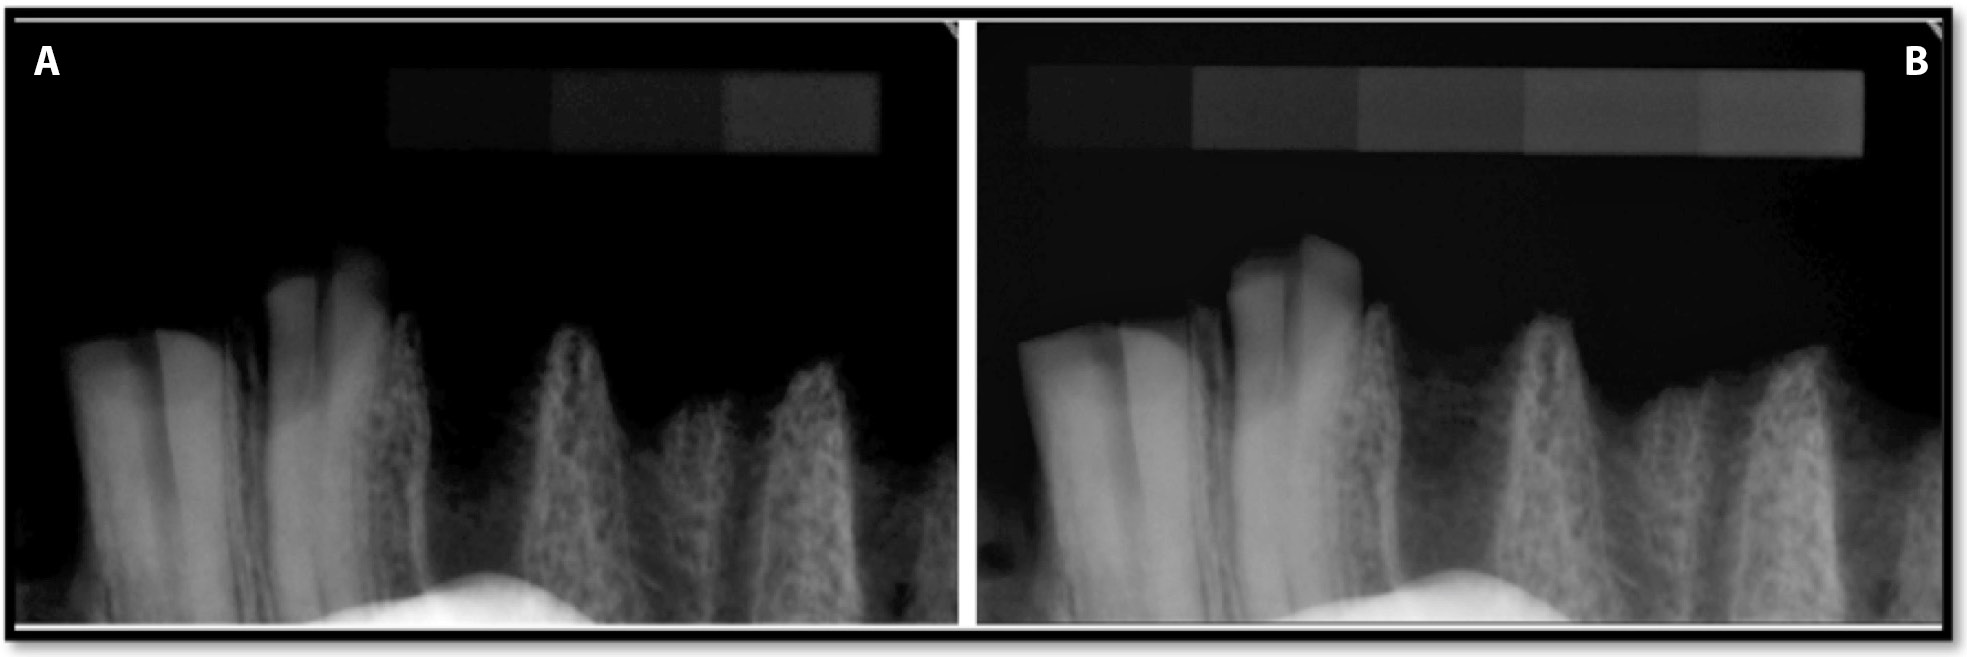

The optical density values of Group B and Group A images captured with exposure times of 0.05 s and 0.125 s are presented in Table 3 and Figure 9. Radiographs of Group B with a bone specimen recorded with an exposure time of 0.125 s are presented in Figure 10. The analysis of the Group B images transferred after exporting with the “export” option (after optimization) revealed that after importing, some structures of the spongy bone (density equivalent to steps 1, 2 and 3 of the phantom) may become undetectable. The use of automated adjustment, after file import, reduced the optical density values of the phantom radiographs from degree 1 to 8, at exposure times of both 0.05 s (from 95.9% to 2.2%) and 0.125 s (from 96.9% to 0.14%) – with the exception of degree 9. The observed ROIs were black and steps 1 and 2 of the phantom also became invisible at shorter (0.05 s) and longer (0.125 s) exposure times. The image background achieves the optical density equal 0 and is totally black. The structures with higher radioabsorption remained visible and the optical density was reduced for steps 6 and 7 of the phantom. It did not change in the case of step 8 and grew in the case of step 9 at both exposure times. The observed problems with the image were the result of using the optimization algorithm repeatedly. In this case, the algorithm should be turned off. Deactivating the optimization algorithm resulted in an optical density that was comparable (identical) with the original one at both exposure times and images that were less dark, displaying the object details more precisely (Figure 9).